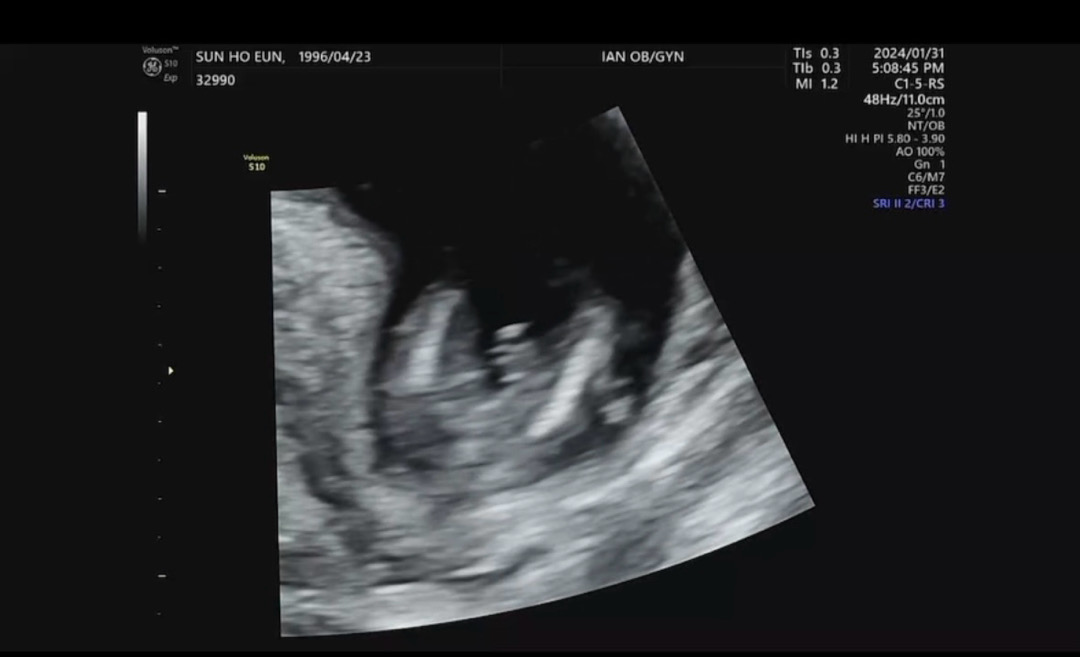

14주 4일차 초음파 봐주세요!!!

설이후에 병원가야해서ㅠㅠ 성별이 너무 궁금하네요ㅠㅠ 고수님들 한번봐주세요!!!